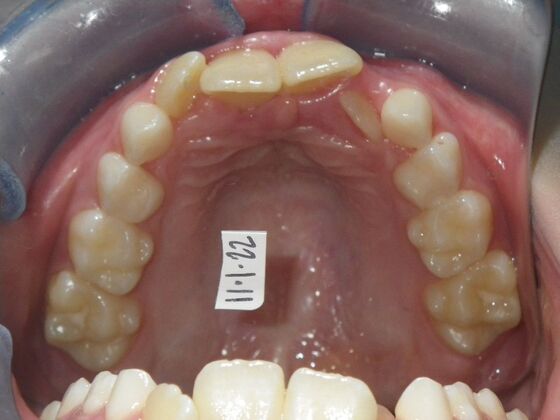

This sweet patient presented with constricted upper and lower arches and blocked out, rotated upper and lower anterior teeth. The upper centrals were leaning backward and had the lower arch captured preventing anterior advancement. Treatment was begun on the upper arch first, followed with placement of lower lip bumper to allow for lateral and anterior development of lower arch. Eventually placed lower brackets with strategic slenderizing of primary teeth to allow permanent incisor to assume their proper placement. All accomplished within 12 months and straight-wire appliances.